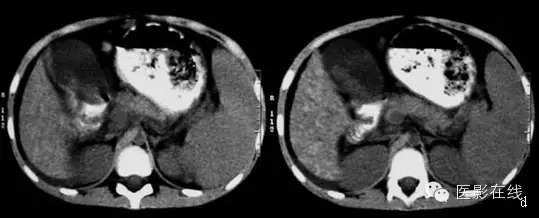

下图肝豆状核变性(a、b、c、d.CT平扫)

【影像所见】

CT平扫:肝脏形态大小正常,肝实质密度普遍增高,可见弥漫性分布高密度小结节影。胆囊增大,胆囊内见不规则高密度影。脾增大,实质密度均匀。

这个病例女性,8岁,CT影像表现肝影增大,质地不均,见多发硬化结节增高影,边缘不光整,肝叶比例失常,脾脏增大,质地均匀。双侧胸腔少量积液。结合病史及眼科检查:患儿有典型的K F环。支持肝豆状核变性(Wilson病)。该病为常染色体隐性遗传性疾病,表现为铜代谢障碍,多见于10~20岁青少年,尿铜量增高,血清铜蓝蛋白降低(<200mg/L, 肝活检含铜量>100mg/g)。(jiangjing)

肝脏密度增高且不均匀,其内可见多个高密度结节影,肝表面不光滑,凹凸不平,脾脏明显增大,脾内未见异常密度灶。眼科检查:患儿有典型的K F环,诊断:肝豆状核变性。(向医生)

①结合临床,考虑肝豆状核变性所致肝硬化,大量肝再生结节形成。②胆囊结石。

肝豆状核变性亦称Wilson 病(WD) ,是先天性铜代谢障碍造成体内铜蓄积,引起组织器官铜毒性损害的常染色体隐性遗传性疾病。铜代谢异常时铜首先沉积于肝脏。临床上可出现肝大和黄疸等肝细胞损害症状,易误诊为肝炎,至晚期肝脏表现为间质纤维化和坏死后肝硬化。CT 及MRI 能充分地显示本病的肝脏改变,大部分病例主要表现为结节性肝硬化。早期肝细胞受损可出现肝脏的肿胀增大,主要为右肝增大,各肝叶间比例正常;以后,肝细胞发生脂肪变性,表现为肝脏密度下降;最后形成肝硬化,表现为肝内多发大小不等、直径1~3 cm、边界尚清的再生结节,平扫时结节呈稍高密度而可区分于周围有脂肪变性的肝组织,增强扫描时结节强化不显著。

本例患者肝脏呈典型的结节性肝硬化改变,虽然颅脑CT检查未发现双侧豆状核对称性低密度灶,但结合患者发病年龄小、尿铜增高、眼底K F环,还是可以确诊为肝豆状核变性的。